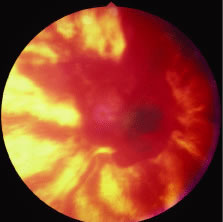

Both herpes simplex virus type 1 and herpes simplex virus type 2 (HSV-1, HSV-2) may cause ARN.20–22 In a single report, CMV particles were identified in and cultured from the retina of an enucleated eye of a nonimmunosuppressed patient suffering from bilateral ARN.23 VZV has been reported most frequently as the viral etiologic agent of ARN.2,3,24–27 We have demonstrated herpesvirus family viral particles in endoretinal biopsy specimens taken from patients in the active stage of the disease who showed an enormous viral load (Fig. 4). These studies, combined with the failure of many enucleated eyes with ARN to demonstrate evidence of viral particles, indicate that the virus is present only in the active stages of the disease and that a gliotic retina will not demonstrate the etiologic agent.28